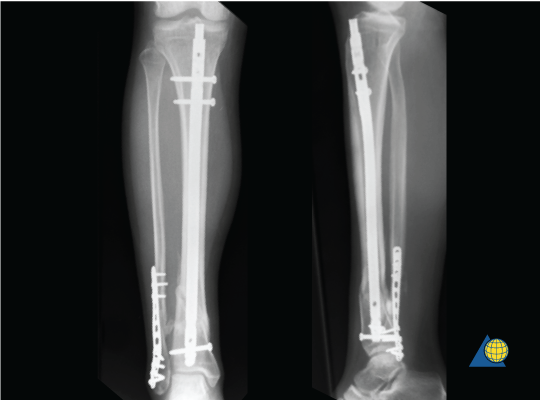

Intramedullary nail